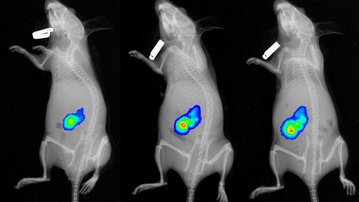

Simova J, Sapega O, Imrichova T, Stepanek I, Kyjacova L, Mikyskova R, Indrova M, Bieblova J, Bubenik J, Bartek J, Hodny Z, Reinis M. Tumor growth accelerated by chemotherapy-induced senescent cells is suppressed by treatment with IL-12 producing cellular vaccines. Oncotarget. 2016 Jul 19. doi: 10.18632/oncotarget.10712. [Epub ahead of print]